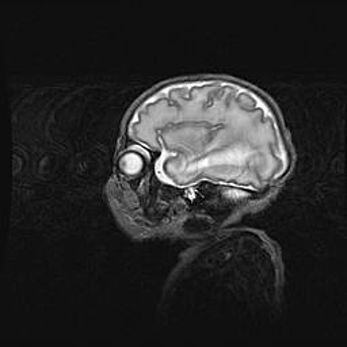

Сообщающаяся гидроцефалия. Кистозная энцефаломаляция головного мозга.

Возраст: 3 месяца 4 дня

Вес: 3100 г

Пол: женский

Окружность головы: 34 см

Срок гестации: 31 неделя

Кистозная энцефаломаляция головного мозга - одна из форм поражения головного мозга в детском возрасте. Характеризуется возникновением множественных и распространённых кист в коре, белом веществе и подкорковых образованиях головного мозга у плодов, новорождённых и детей раннего возраста. Развитие кистозной энцефаломаляции связано с внутриутробной асфиксией и гипотонией, родовой травмой, тромбозом синусов, пороками развития сосудов, инфекциями, сепсисом и другими причинами. Наиболее значимые инфекционные агенты: вирусы простого герпеса, цитомегалии, краснухи, токсоплазмы, энтеробактерии, золотистый стафилококк и другие.